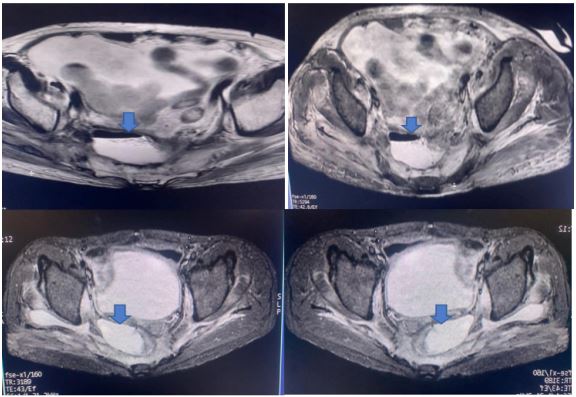

Case capsule 1

A 59-year-old man has complained of pus and mucus discharge from the anal region, as well as intermittent fever episodes, for the past two years. Three years ago, he developed symptoms of per rectal bleeding and was diagnosed with Carcinoma rectum, for which he received three cycles of neoadjuvant radiotherapy followed by laparoscopic anterior resection with a defuncting descending colostomy. He was discharged on post-operative day 8, with no issues reported. Adjuvant Chemotherapy was administered in 13 cycles. After 6 months of surgery, a CT abdomen was performed, which showed post-op changes in the pelvis with Pelvic peritoneal fat stranding and widening of the presacral space. He was having repeated episodes of fever with chills and pus discharge per anus that were resolved with IV antibiotics. After 6 months, an MRI of the pelvis revealed a significant collection of size 9.1 x 5.2 x 8.8 cm with air loculi at the presacral area-most likely a controlled leak (Figure 2). The conservative approach was continued for another six weeks, during which an intermittent fever with mucus and pus discharge from the anal region persisted. A colonoscopy was performed, which showed the cavity and confirmed the findings (Figure 4). Endovac sponges were sutured to RT and placed directly into the cavity with the help of a colonoscope after debriding and irrigating the cavity. After applying post-E-VAC therapy, the patient improved and had no fever after 48 hours. The procedure was repeated on an OPD basis four more times, with the endovac in place for five days each. At each session of endoscopy, there was a reduction in the size of the sponge used and considerable improvement in terms of the size of the cavity and the amount of slough (Figure 5). The cavity completely healed 10 weeks after E-VAC therapy, and the patient has been asymptomatic for the past 4 months. A CT scan showed complete resolution of the leak.

Figure 3: MRI pelvis showing collection in presacral area.